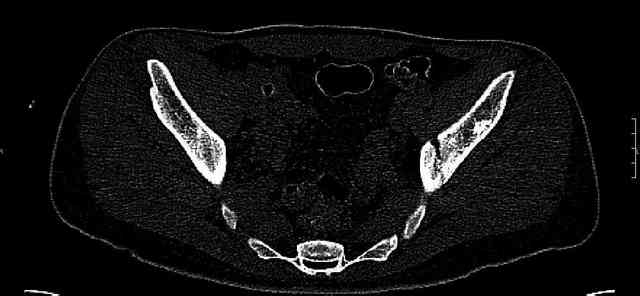

Мужчина 33 лет получил травму в шахте (придавило вагонеткой) 6 недель назад. Изолированное повреждение вертлужной впадины.

В местной больнице отлежал несколько недель на вытяжении. После выписки амбулатрный травматолог направил в институт. На сегодня, похоже, уже имеется неправиильное сращение. См. картинки.

Dear all,A male 23 y.o. injured 6 weeks ago - mine trauma, impacted by a carriage. Isolated injury of the acetabulum. At the initial hosptial was on bed traction some weeks. After discharge visited anotheк orthopaedic surgeon who referred him to our unit. To date looks like a malunion. Images attached. The question is about what to do now - either leave it as is or perform open reduction? If the latter what approach, reduction manoeuvres and fixation would you advice? Thx in advance!

What is your indication for surgical management? What kind of fracture do you think it is? It looks like a transverse type although it has been a couple of years since I looked at an acetabular fracture.

My concern would be that the risk of leaving it malreduced is very high. It appears to be primarily a gap rather than a step in the articular surface. Do you have any CT views that show an articular step?

The last two images from the 3-D CT scan certainly makes the fracture look worse than the plan radiographs.